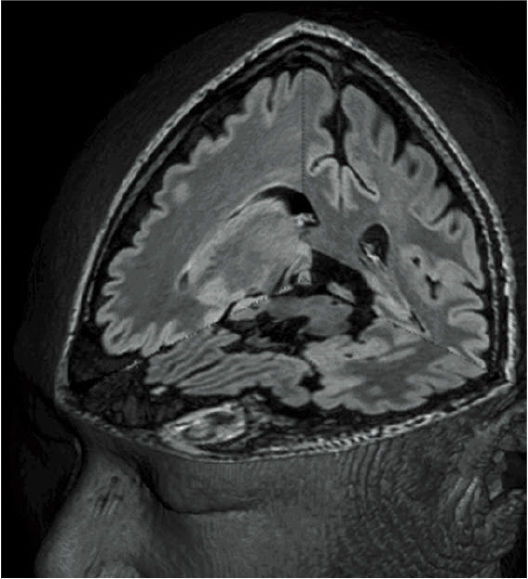

Клинические изображения аппарата МРТ Fujifilm ECHELON Smart

Fujifilm ECHELON Smart — это современная система магнитно-резонансной томографии 1.5 Тесла, спроектированная для достижения оптимального баланса между качеством изображения, скоростью исследования, комфортом пациента и экономичностью эксплуатации. Аппарат МРТ объединяет в себе инженерные традиции японской школы точного машиностроения и инновационные алгоритмы обработки изображений Fujifilm, создавая мощную платформу для широкого спектра клинических задач — от нейровизуализации и сосудистых исследований до МРТ брюшной полости, суставов и позвоночника. Томограф построен на базе высокопроизводительных подсистем SmartENGINE, SmartSPEED, SmartQUALITY и SmartCOMFORT, обеспечивающих стабильную работу, высокую чувствительность и превосходное соотношение сигнал/шум при низких эксплуатационных затратах.